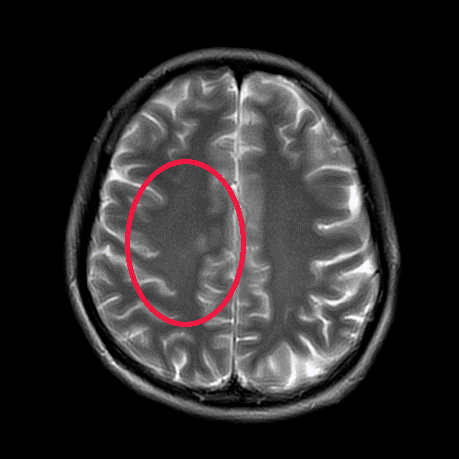

因为出现双下肢乏力、影响行走前来就诊

经过一系列检查确诊为

肺腺癌伴颅内、多发淋巴结转移

▲治疗前

▲治疗后1月

▲治疗后2年半